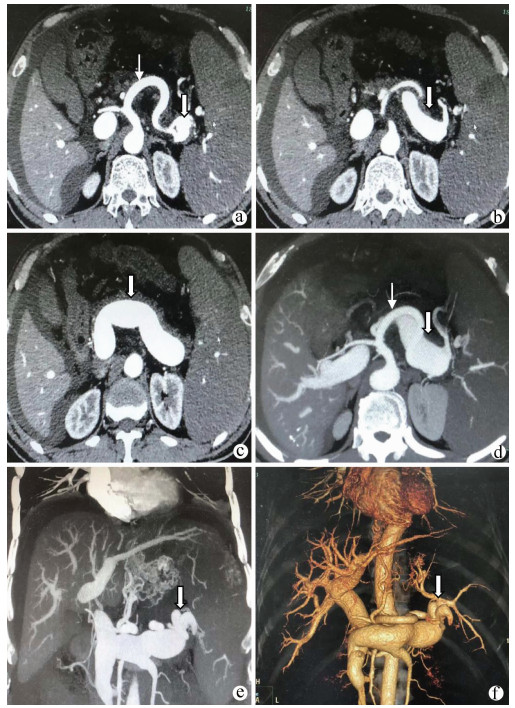

A case of splenic arteriovenous fistula with abdominal pain and gastrointestinal bleeding as the first symptoms

Yuanyuan CAI, Zhongwen WU, Juan LU

2021, 37(5): 1186-1188. DOI: 10.3969/j.issn.1001-5256.2021.05.043

Abstract(1011) HTML (291) PDF (2876KB)(49)

Abstract: